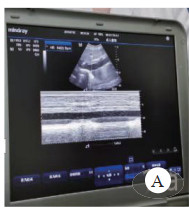

启动ECMO之前完善床旁心脏超声及CT检查。超声提示下腔静脉宽且恒定(图 1),右心增大明显呈D字征,左心EF < 30%。肺部超声提示双侧大量B线(图 2)

| 图 1 下腔静脉宽恒定 Fig 1 Constant width of inferior vena cava |

| 图 2 肺部超声大量B线 Fig 2 Large B-line of lung ultrasound |